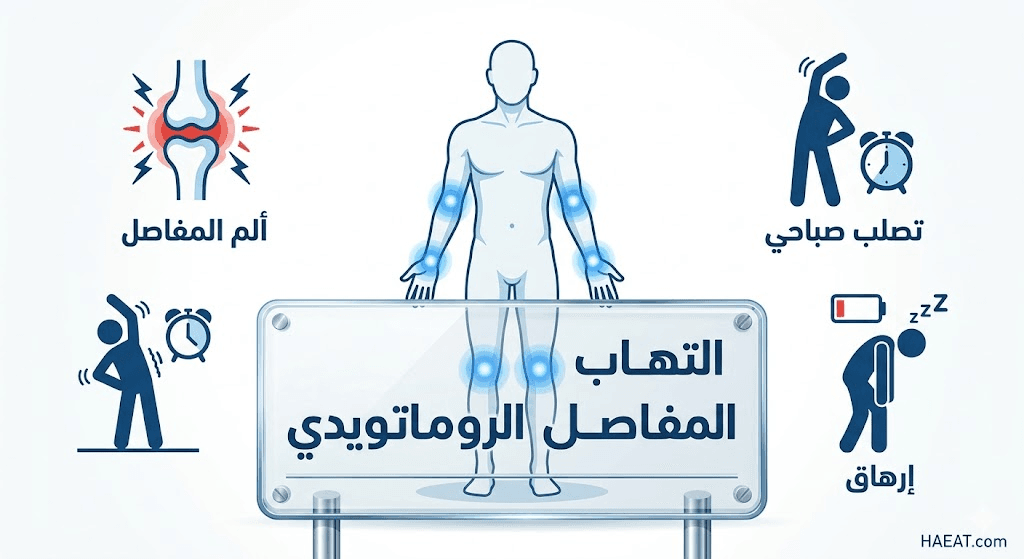

تتسم المظاهر السريرية لهذا المرض بالتنوع، حيث تظهر الأعراض بشكل تدريجي في البداية قبل أن تتفاقم لتشمل مفاصل متعددة في وقت واحد وبشكل متناظر.

- التيبس الصباحي الشديد: الشعور بصلابة المفاصل عند الاستيقاظ، وهو عرض يستمر عادة لأكثر من 30 دقيقة إلى ساعة كاملة قبل أن يبدأ في التلاشي تدريجياً.

- آلام المفاصل النابضة: يعاني المرضى من آلام مزمنة في مفاصل الرسغ، اليدين، والقدمين، وتزداد هذه الآلام سوءاً أثناء فترات الخمول أو الراحة الطويلة.

- الإعياء المزمن والوهن: يشعر المصاب بتعب عام غير مبرر، يشبه أعراض الإنفلونزا المستمرة، نتيجة استجابة الجسم الدفاعية الكثيفة وتدفق السيتوكينات الالتهابية.